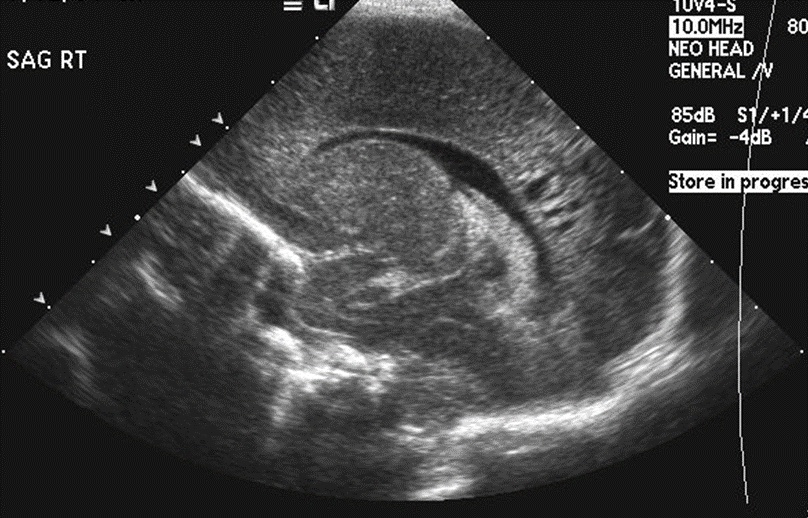

Info Images Findings Impression Reco/Acuity Case Images View Images / Launch Visage Case Notes History Full term infant. We are asked to evaluate posterior fossa cyst. Exam Gray scale and Doppler Ultrasonographic examination of the head. Prior Study N/A Dicom View Reference Material

Section 1 Submit Findings Case149 Findings Brain The brain is immature. Yes No There is under-sulcation and open sylvian fissures. Yes No There is/are multiple hypoechoic areas in the periventricular white matter. Yes No There is/are multiple hyperechoic areas in the periventricular white matter. Yes No There is diffuse cerebral edema with diffusely increased echogenicity of the brain parenchyma and loss of grey white matter differentiation. Yes No The thalami/basal ganglia are hypoechoic. Yes No There is periventricular calcification. Yes No There is intra-parenchymal calcification. Yes No CSF spaces/ventricular system There is a prominence of the extra axial fluid spaces. Yes No There are debris/septations in the extra axial fluid spaces. Yes No There are debris/septations in the ventricles. Yes No There is a subdural collection on the right/left side. Yes No There is prominence of the ventricular system. Yes No There is an asymmetry of the ventricular system. Yes No There is a cavum septum pellucidum. Yes No There is a midline shift towards right/left. Yes No The choroid plexus is bulky/lobulated. Yes No There is a choroid plexus cyst measuring… Yes No There are debris/clots in the occipital horn. Yes No There is a posterior fossa cyst measuring… Yes No The tentorium is elevated/depressed. Yes No The lateral ventricle/s are dilated. Yes No The third ventricle is dilated. Yes No The 4th ventricle is dilated. Yes No There are pseudo cysts. Yes No Germinal matrix hemorrhage (Only in the premature infants): Please do not answer if the patient is a full term. There is a germinal matrix hemorrhage, consistent with a grade I hemorrhage. Yes No There is an intraventricular extension consistent with a grade II hemorrhage. Yes No There is an intraventricular extension with the dilatation of ventricles, consistent with a grade III hemorrhage. Yes No There is an intra-parenchymal extension, consistent with grade IV hemorrhage. Yes No On color Doppler examination, the Resistive index in the anterior cerebral artery is… There is a loss of the diastolic flow on the Doppler exam. Yes No There is altered vascularity on Doppler imaging. Yes No There is an AVM in the region of… Yes No